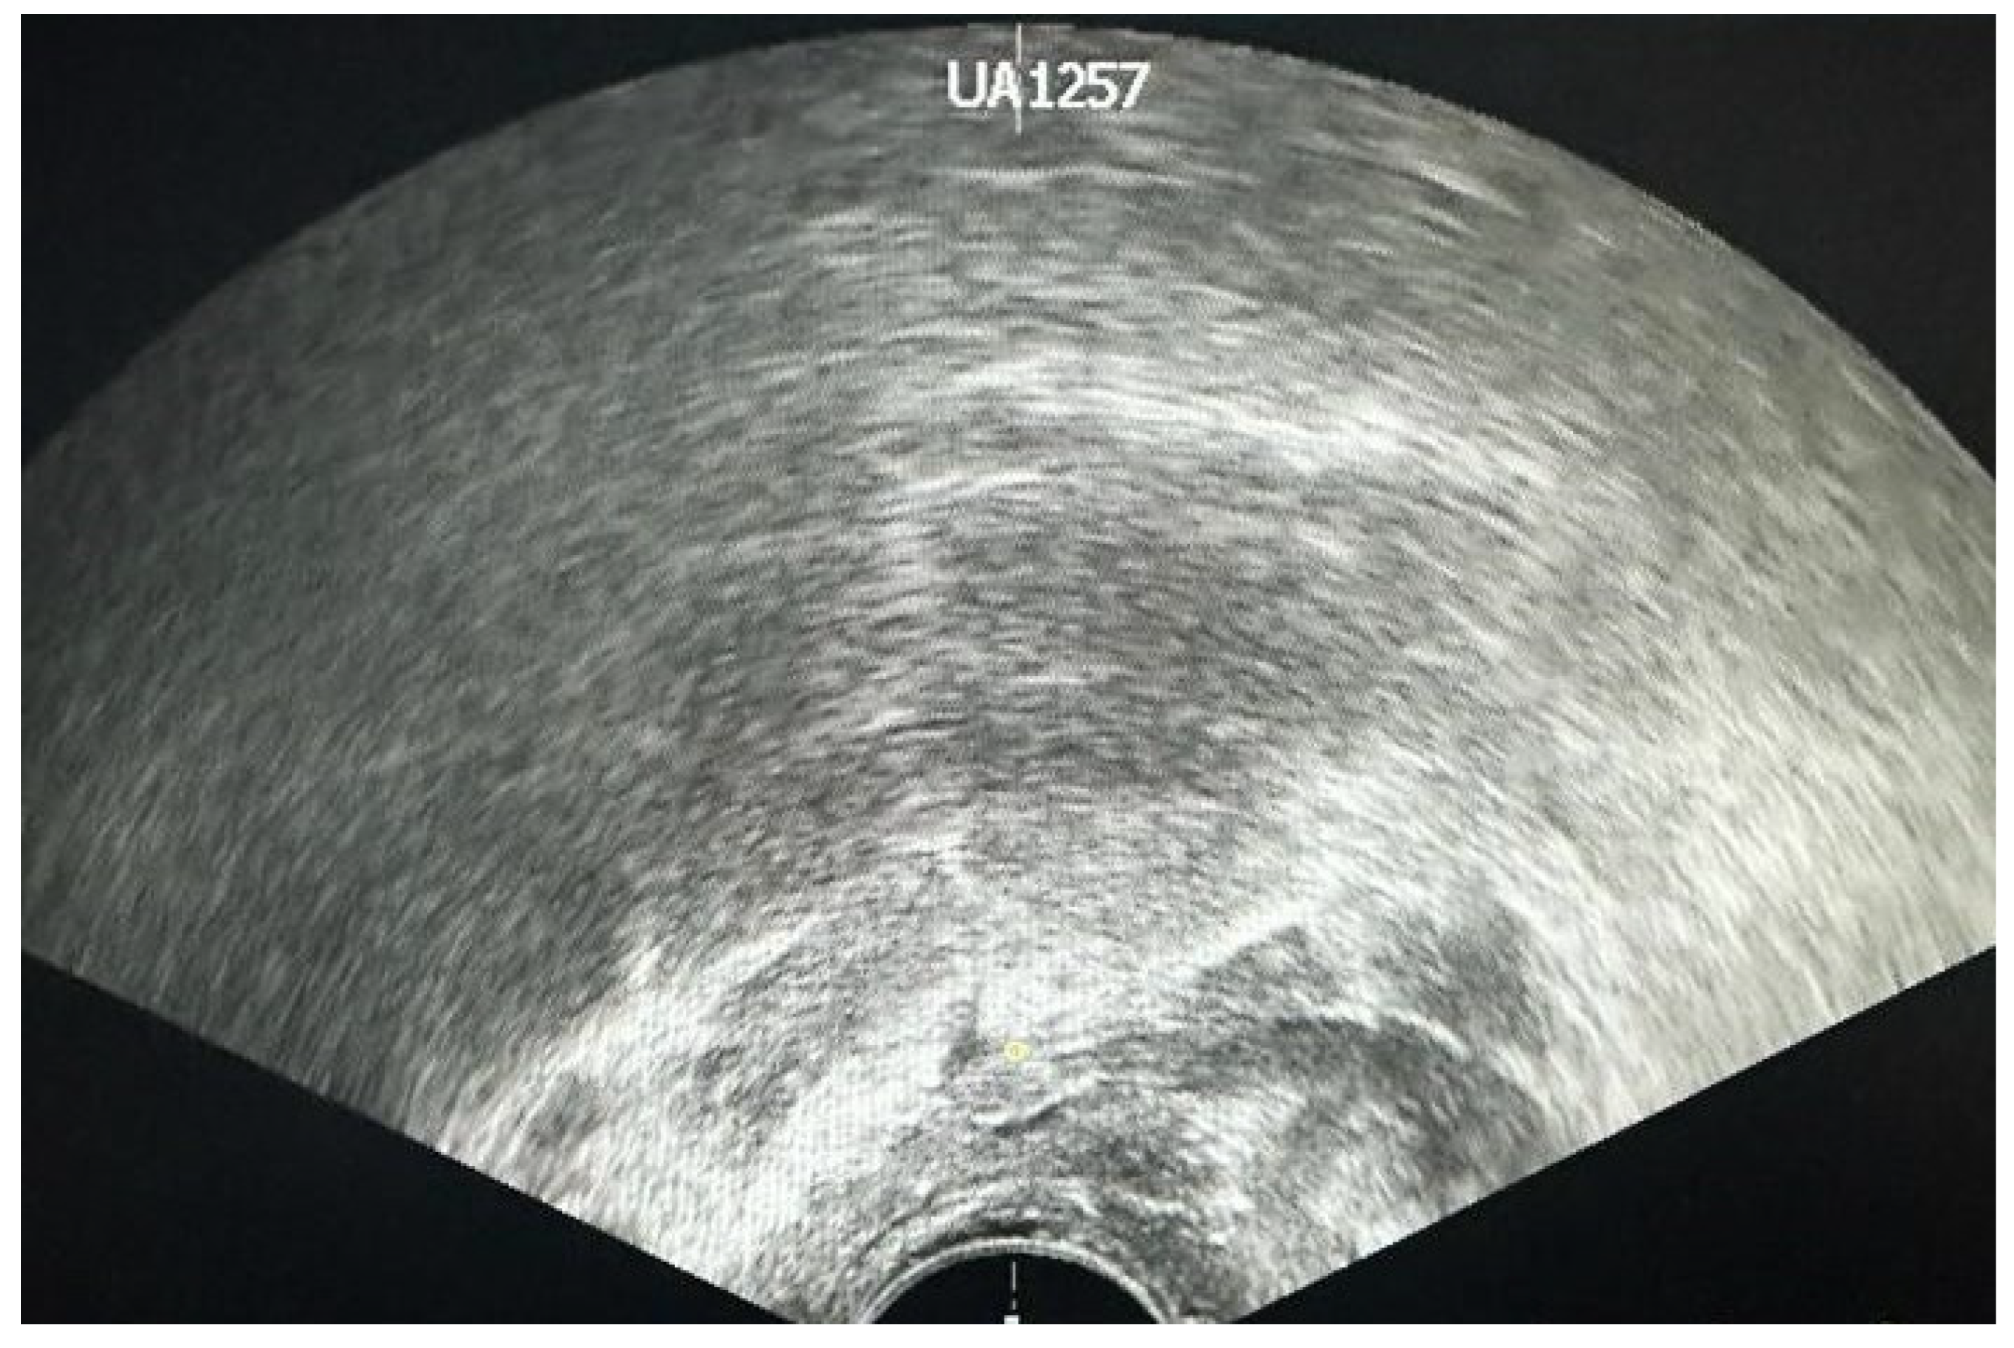

4. Transrectal Ultrasound (TRUS)-Guided Prostate Biopsy

6. Technical Difficulties

6.2. Prostatic Diameter and Volume